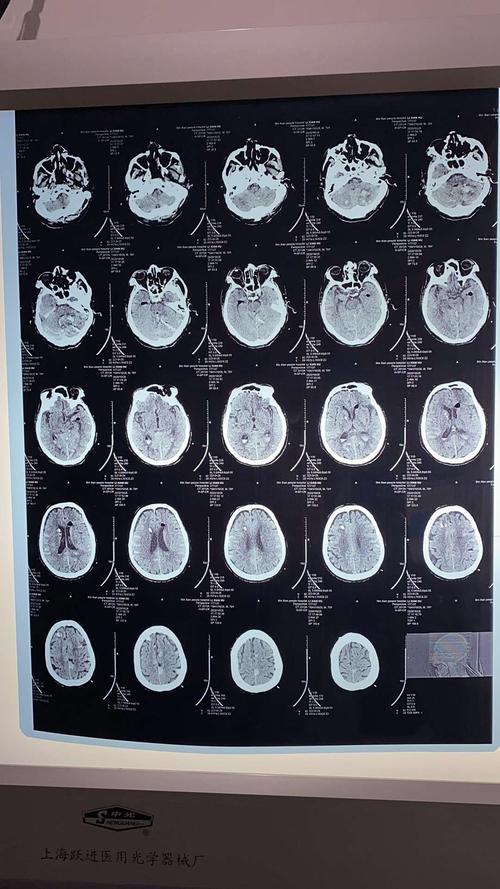

脑出血片子图片解析

脑出血片子图片解析,脑出血检查报告单图片

脑出血ct影像表现图片

脑出血ct图片解说图

脑出血片子

脑出血图片ct

脑出血ct